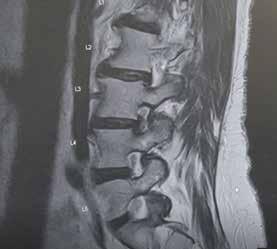

Consider the plight of a patient dealing with new back or neck pain. The sheer complexity of the spine – with all of its related bones, nerves and muscles – can make diagnosis and treatment a challenge. But for patients dealing with debilitating pain, the most important thing is quickly finding the right specialist or treatment to help them get better.

The new Orlando Health Spine Center brings together both orthopedic and neurosurgical physicians who specialize in spine surgery.

With 16 locations across Central Florida, the Orlando Health Spine Center makes the referral process for primary care physicians significantly more streamlined.